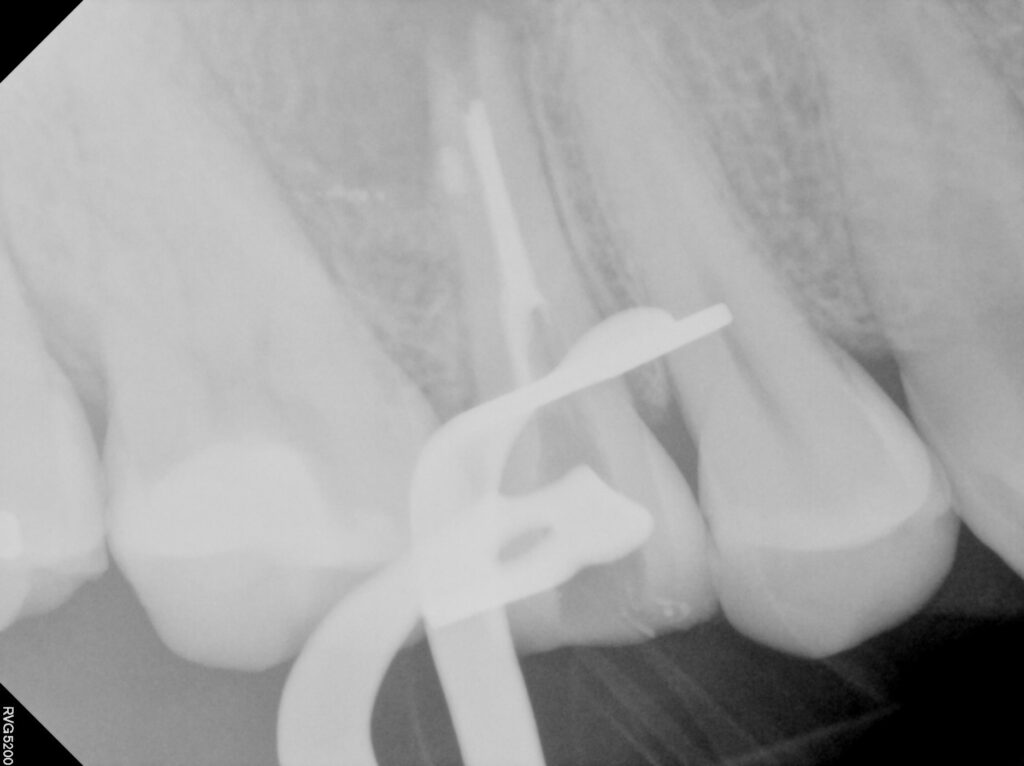

재신경치료의 과정입니다.

치료 시 근관 내 MTA 충전까지

함께 진행하였습니다.

재신경치료는 기존의 근관 충전재를 제거하고

감염된 부위를 다시 소독한 뒤

정밀하게 재충전하는 과정을 거쳐야 하기 때문에

더 정교한 기술과 경험이 요구됩니다.